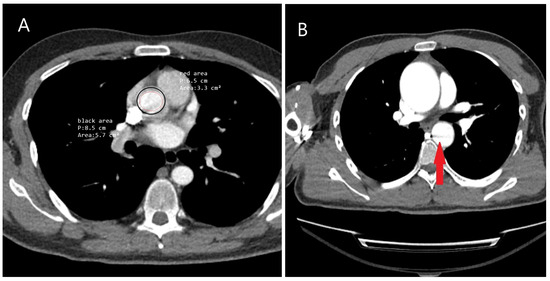

5.2.3. Computed Tomography